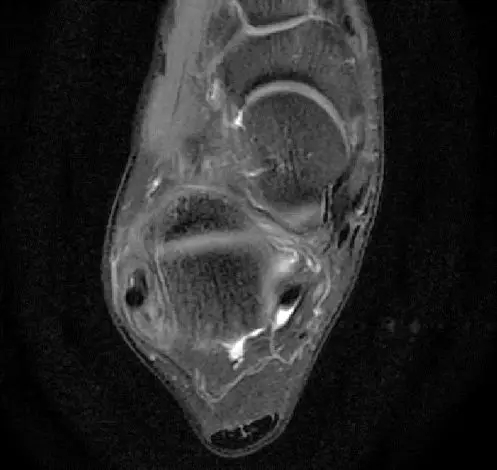

此片可以看到韧带结构消失,T2相高信号,整体韧带增粗,松弛,腓骨肌腱内侧,跟绯肌腱的形态完全消失,它的韧带也是松弛增粗的。所以考虑是踝关节距腓前韧带的损伤。